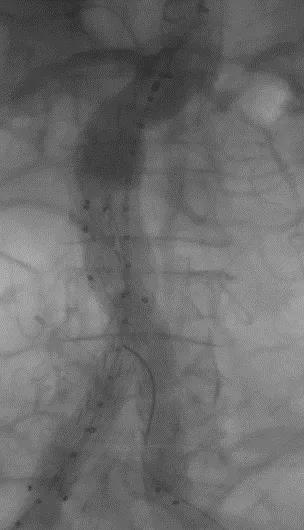

此次研究,纳入腹主动脉瘤的最大直径为85mm,平均直径为50.78mm;最短瘤颈长度为11mm,平均长度为31.34mm;最大肾下成角为74.6度,平均角度为32.48度。从动脉瘤最大直径变化来看,经过腹主动脉腔内治疗后,在出院前和术后6个月都有所减小。 在此次研究中,先健Yuranos™新一代腹主动脉覆膜支架系统临床试验初步展现了优秀的临床试验结果,其30天内MAE发生率低,安全性得以验证;而且由于该产品的柔顺性有较大提升,输送器直径减小,对于短瘤颈和角度大的病例是更好的选择。 入组病例展示: 病例一:男性,年龄69岁,既往高血压,糖尿病病史。术前腹主动脉瘤直径67.3mm,近端瘤颈长度23.2mm,近端锚定区直径21.2mm,肾下成角60.5度。 术中从右侧股动脉穿刺,选用先健型号为AB-2412-50-120的主体支架,支架近端定位于右肾动脉开口处,后释放打开裸支架,并向下释放主体短分支,左侧输送进入先健髂动脉延长支架IE-1416-100,并释放,保留左侧髂内动脉。接着释放主体长分支,右侧输送进入先健髂动脉延长支架IE-1424-80,并释放,保留右侧髂内动脉。 手术顺利,无内漏,持续时间1小时10分钟。术后CTA检查,支架形态良好,无内漏。详见下图: 术前影像 术中影像 出院前影像 术后6个月影像 术后1年影像 病例二:女性,年龄72岁,既往高血压,静脉曲张病史。术前腹主动脉瘤直径48.81mm,近端瘤颈长度16.15mm,近端锚定区直径18.43mm,肾下成角66度。 术中从右侧股动脉穿刺,选用先健型号为AB-2412-50-140的主体支架,支架近端定位于右肾动脉开口处,后释放打开裸支架,并向下释放主体短分支,左侧输送进入先健髂动脉延长支架IE-1414-120,并释放,保留左侧髂内动脉。接着释放主体长分支,右侧输送进入先健髂动脉延长支架IE-1414-80,并释放,保留右侧髂内动脉。